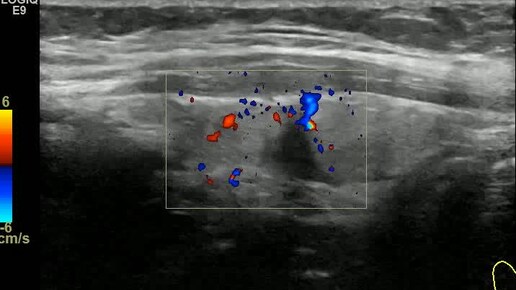

Видео к статье "Стратификация узлов щитовидной железы. TI-RADS-5" https://dzen.ru/a/ZwTJQTbM3zpM5Y6F

Ультразвуковые находки от врача УЗД Зорина Я.П.